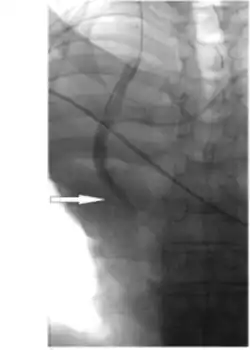

_(1)_(1).png.webp)

Hydrophilic catheter treatments can also be used through placement of the catheter through the femoral veins to access the stenosis in the vena cava to measure haemodynamic and angiography. [6] Angiography allows for visualisation of the stenosis in the vena cava and measurements of the pressures and length of narrowing can be obtained from the technique, including the narrowest diameter of the stenosis. [6] Balloon angioplasties can also be performed in the narrowed vena cava using Sterling balloons. [6] Dilations are also performed with higher pressure Dorado balloons, using the same wire as the Sterling balloon. [6] Sustained results of increased flow and significant reduction in obstructions following stent implantation occurs from balloon angioplasty treatments. [6]